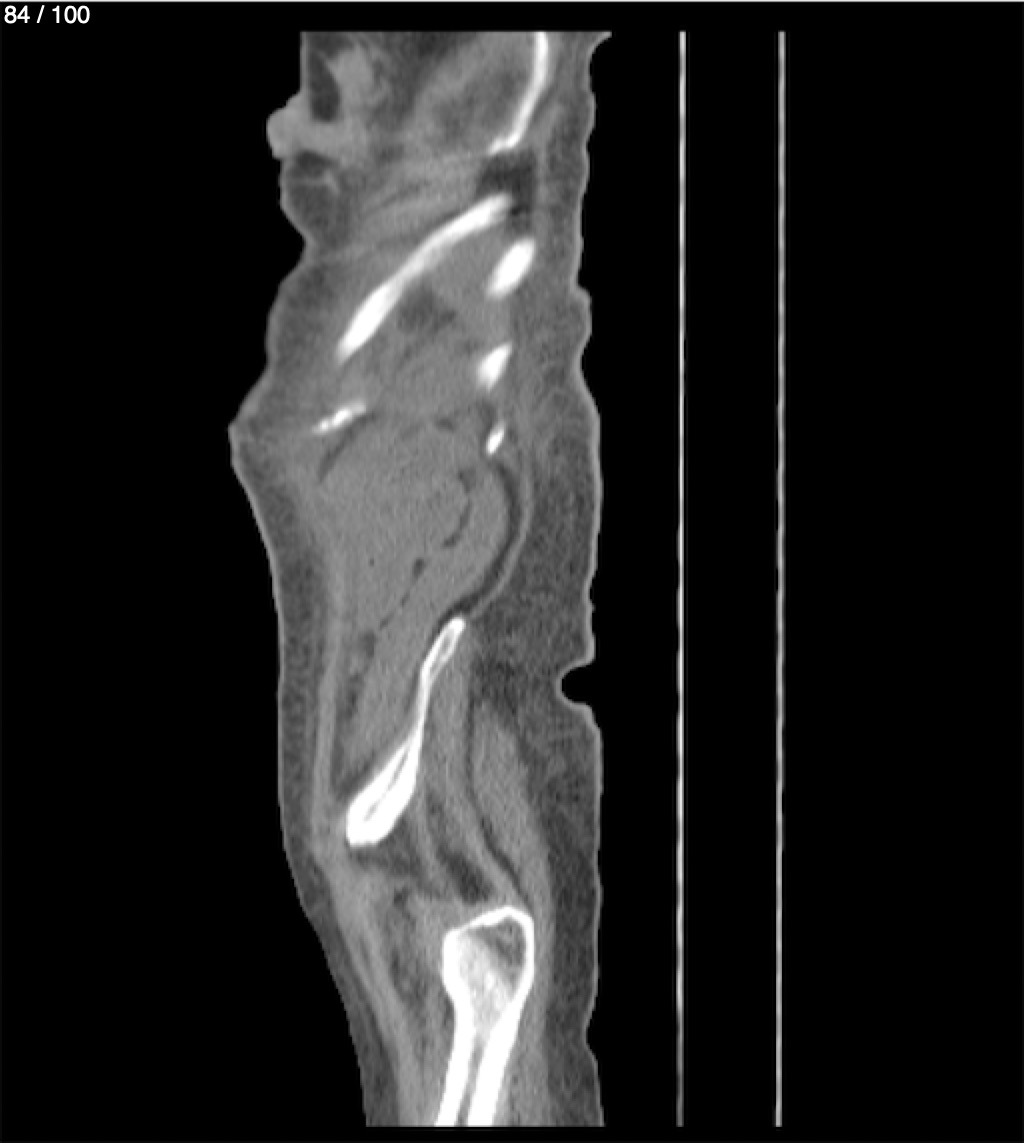

Hilda Geronimo Mendez 60A - T.C Abdomen Simple